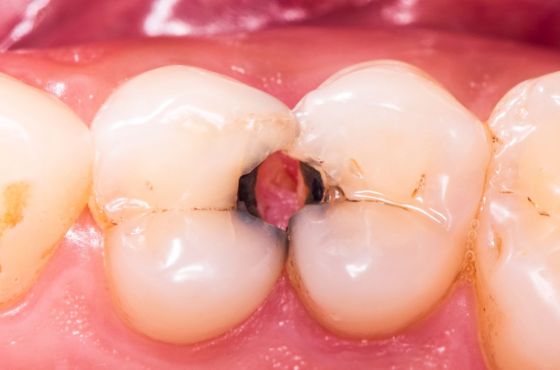

Las caries se originan cuando las bacterias de la boca descomponen azúcares de los alimentos y producen ácidos que dañan el esmalte dental. Si el daño alcanza la pulpa del diente, donde se encuentran nervios y vasos sanguíneos, puede formarse un absceso dental. En este punto, la infección puede propagarse más allá del diente.